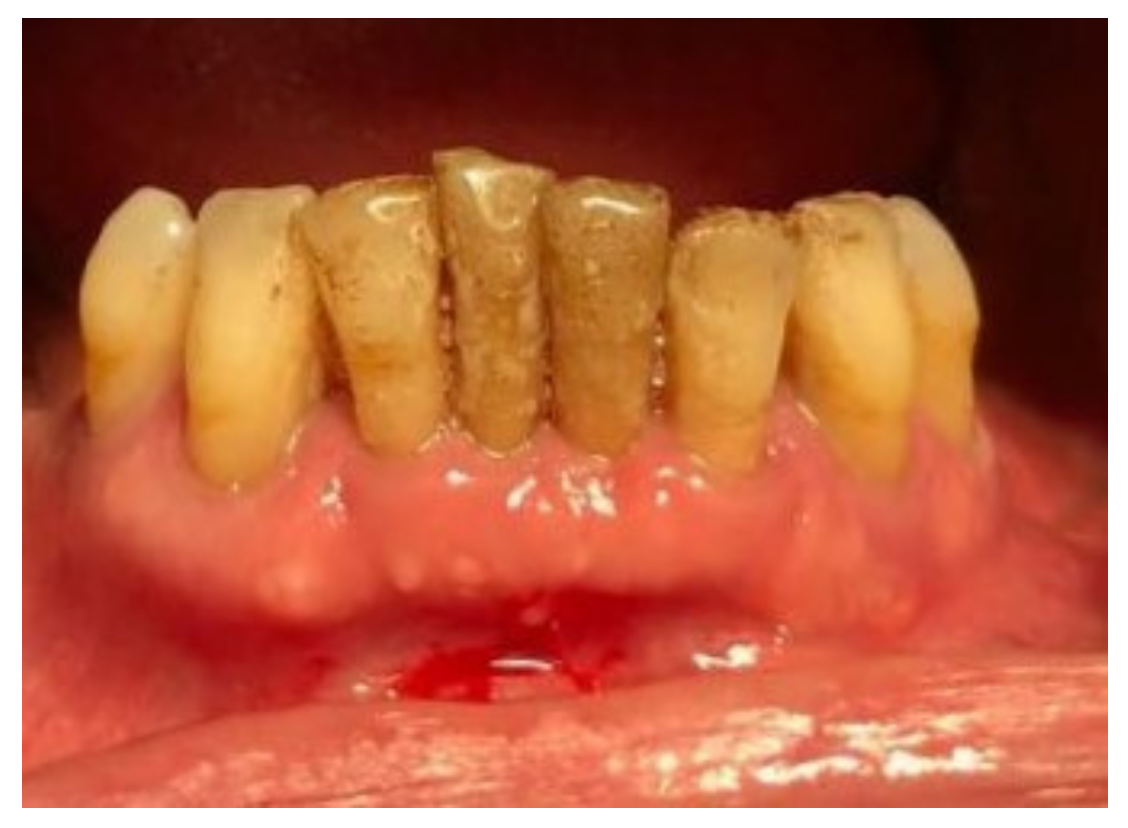

| Tissue colour: | 50% of gingiva red |

| Granulation tissue: | Present | |

| Incision margin: | Not epithelialized, with loss of epithelium beyond incision margin | |

| Suppuration: | Present | |

| Incision margin: | Not epithelialized, with connective tissue exposed | |

| Suppuration: | None | |

| Granulation tissue: | None | |

| Incision margin: | No connective tissue exposed | |

| Tissue colour: | 25% of gingiva red |

| Tissue colour: | All tissues pink |

| Suppuration: | None |